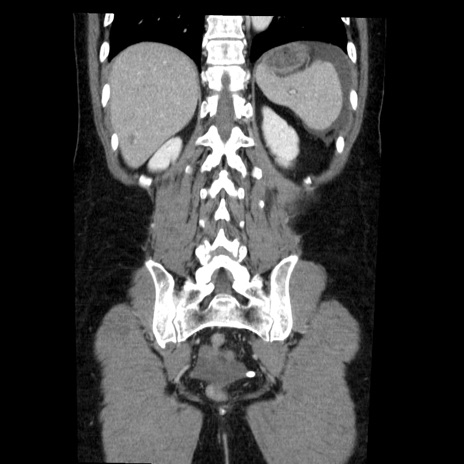

症例6(冠状断像)

【症例】50歳代女性

【主訴】下腹部痛

【現病歴】本日朝より下痢2回あり。 昼食を食べた後、嘔吐3回、下腹部痛認め、症状軽快せず、当院救急搬送。

最終食事:本日昼(生ものなし)。 昨日の夜、刺身を食ぺたとのこと。周囲に同様の症状の者なし。普段、排便は毎日あるとのこと。

【既往歴】卵巣癌術後(8年前に当院で卵巣摘出)

【身体所見】 意識清明、腹部:平坦、腸蠕動音→、やや硬、下腹部自発痛・圧痛あり、反跳痛あり、筋性防御なし。

【データ】WBC 16000、CRP 0.01